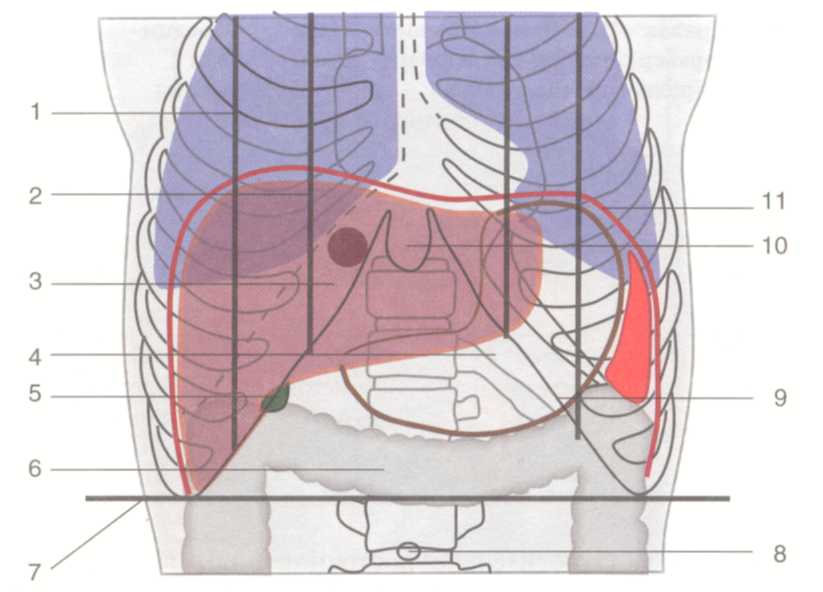

Скелетотопия: Относительно постоянна лишь верхняя граница печени. Верхняя и нижняя границы печени представлены ниже и на рис. 1.24.

| Граница | Средняя подмышеч- ная линия | Средне- ключичная линия | Передняя срединная линия | Левая парастер- нальная линия |

| Верхняя | X межреберье | Четвертое межреберье | Немного выше ос- нования мечевидно- го отростка | V межребе- рье |

| Нижняя | X межреберье | Середина между пуп- ком и ме- чевидным отростком | Vмежребе- рье |

Граница нижнего края печени может сильно меняться, особенно при патологических состояниях органа. В норме нижний край печени справа по средней подмышечной линии соответствует десятому межреберью, затем проходит по краю реберной дуги, у правой среднеключичнои линии выходит из-под нее и идет косо влево и вверх, проецируясь по срединной линии тела на середине расстояния между пупком и основанием мечевидного отростка.

Левую часть реберной дуги нижний край печени пересекает примерно на уровне хряща VI ребра.

Границы печени зависят от ее размеров, формы и положения. Кроме описанных границ, встречаются крайние формы изменчивости в ее положении: дорзопетальное – когда печень наклонена кзади, в таких случаях хорошо видна ее нижняя поверхность и легко доступен желчный пузырь; вентропетальное – печень наклонена кпереди, в таких случаях доступ к нижней ее поверхности весьма затруднен. Встречаются также фронтальные смещения печени. При смещении вправо (dextropositio) край печени может достигать гребня подзвдошной кости, при смещении влево (sinistropositio) – может смещаться кнаружи от левой среднеключичной линии.

Рис.1.24. Голотопия печени.

1 — linea medioclavicularis; 2 — linea parasternalis; 3 — hepar; 4 — gaster; 5 — vesica biliaris;

6 — colon transversum; 7 — linea bicostarum; 8 — umbilicus; 9 — arcus costalis;

10 — processus xiphoideus; 11 — diaphragma.